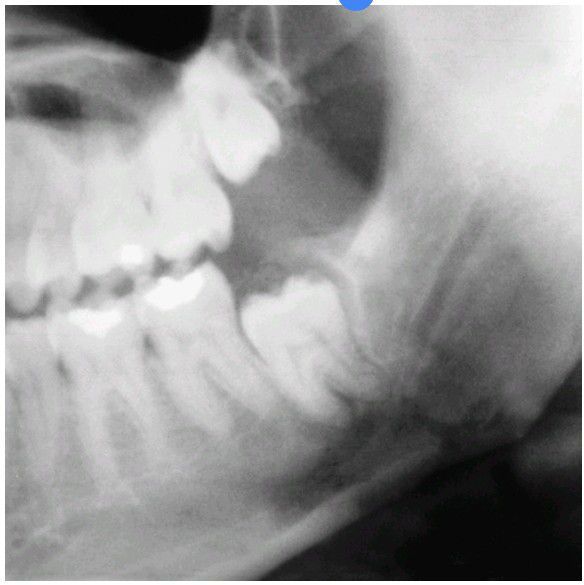

Impacted tooth and fracture

Fracture of a mandible, which occurred through the location of an impacted third molar.